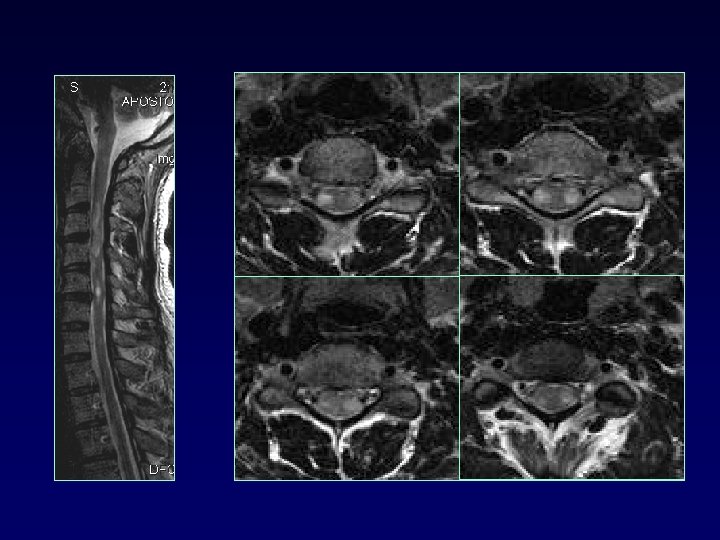

SPINAL CORD • • 50 -90% MS up to 25% only site involved cervical dorsolateral, < 2 vertebral bodies < half transverse diameter Multifocal Cord atrophy